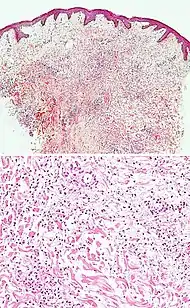

| Kaposi’s sarcoma in patch stage | The patch stage typically shows irregular proliferation of jagged vascular channels in the dermis below an integral epidermis. The so-called promontory sign is sometimes found in patch stage lesions and denotes vascular spaces surrounding pre-existing blood (see image).[24]

vessels |

![]() |